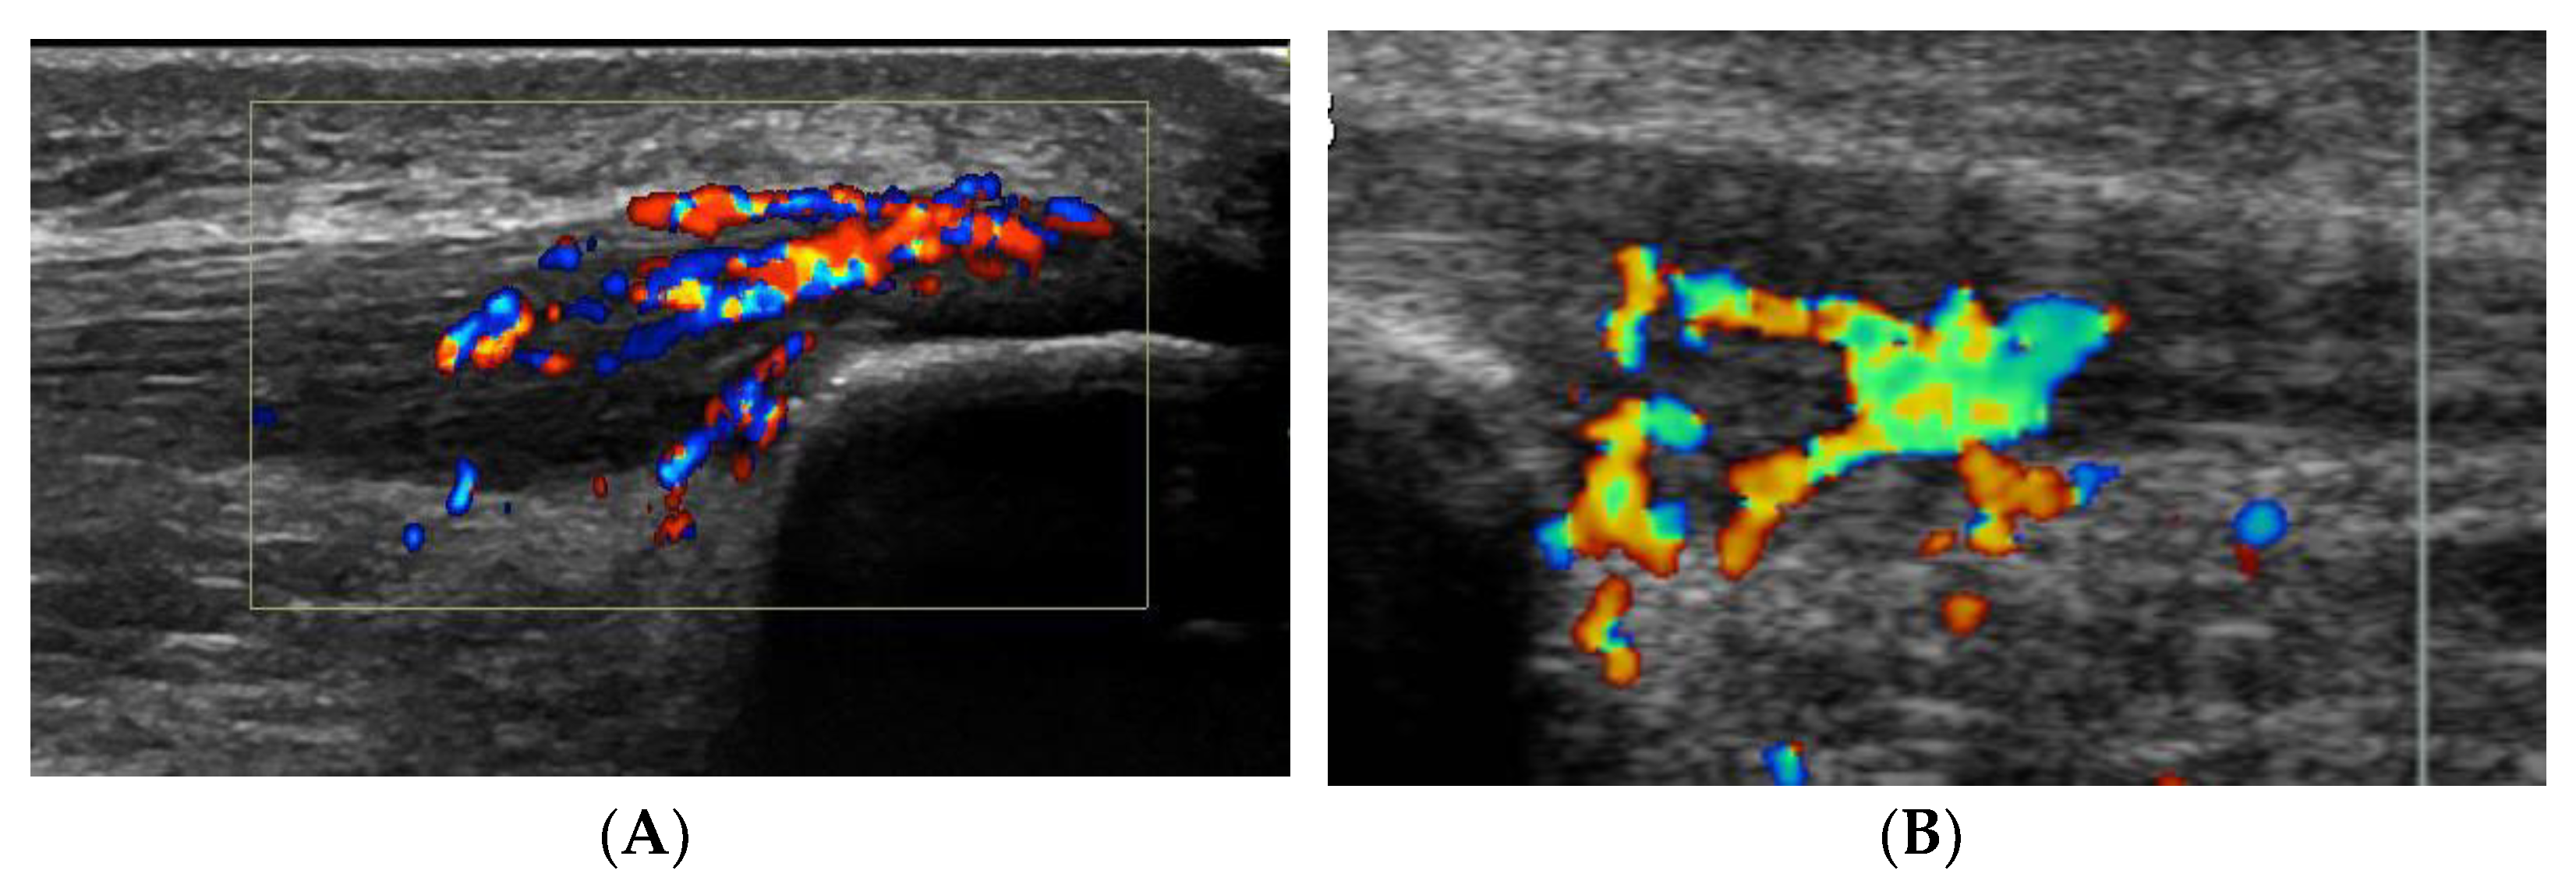

Six patients (4 men and 2 women; mean age 23 years, range 17–31 years) were included. All patients were sports active and had suffered from ultrasound and Doppler verified patellar tendinopathy in the proximal part of the patellar tendon for more than 3 months [5]. In all deleted word these patients, there was also severe tenderness localized on the superficial side of the proximal patellar tendon, and ultrasound+Doppler examination showed a thickened paratenon including high blood flow in that region (Figure 1A).

As described above, all ultrasound+Doppler examinations showed a thickened para-tenon including high blood flow in the superficial peritendinous region (Figure 1A). This was in contrast to the majority of patients with patellar tendinopathy where there is a normal paratenon and normal blood flow (Figure 1B). All tissue specimens contained large portions of loose connective tissue with high numbers of blood vessels and also fat tissue. There were multiple nerve fascicles and sprouting nerve fibers as evidenced by evaluation for HTX and β-tubulin reactions (Figure 3 and Figure 4). Often those nerves were found in close vicinity to blood vessels and perivascular in blood vessel walls (Figure 3). Sensory innervation (CGRP positive nerve fibers) was mostly found in axons of nerve fascicles (Figure 4 and Figure 5). Sympathetic innervation (TH positive nerve fibers) was found both in nerve fascicles and perivascular in big and small blood vessels.

Figure 1. (A,B). Ultrasound and Doppler picture from 2 patients suffering from chronic painful patellar tendinopathy. There is a thickened proximal patellar tendon, including irregular tendon structure, hypo-echoic regions and high blood flow on the dorsal side of the tendon. (A): This patient also had severe tenderness on the superficial side of the proximal tendon, where there was a localized thickening of the paratenon including high blood flow. (B): This patient had no tenderness on the superficial side of the proximal tendon, where there was a normal paratenon and normal blood flow.